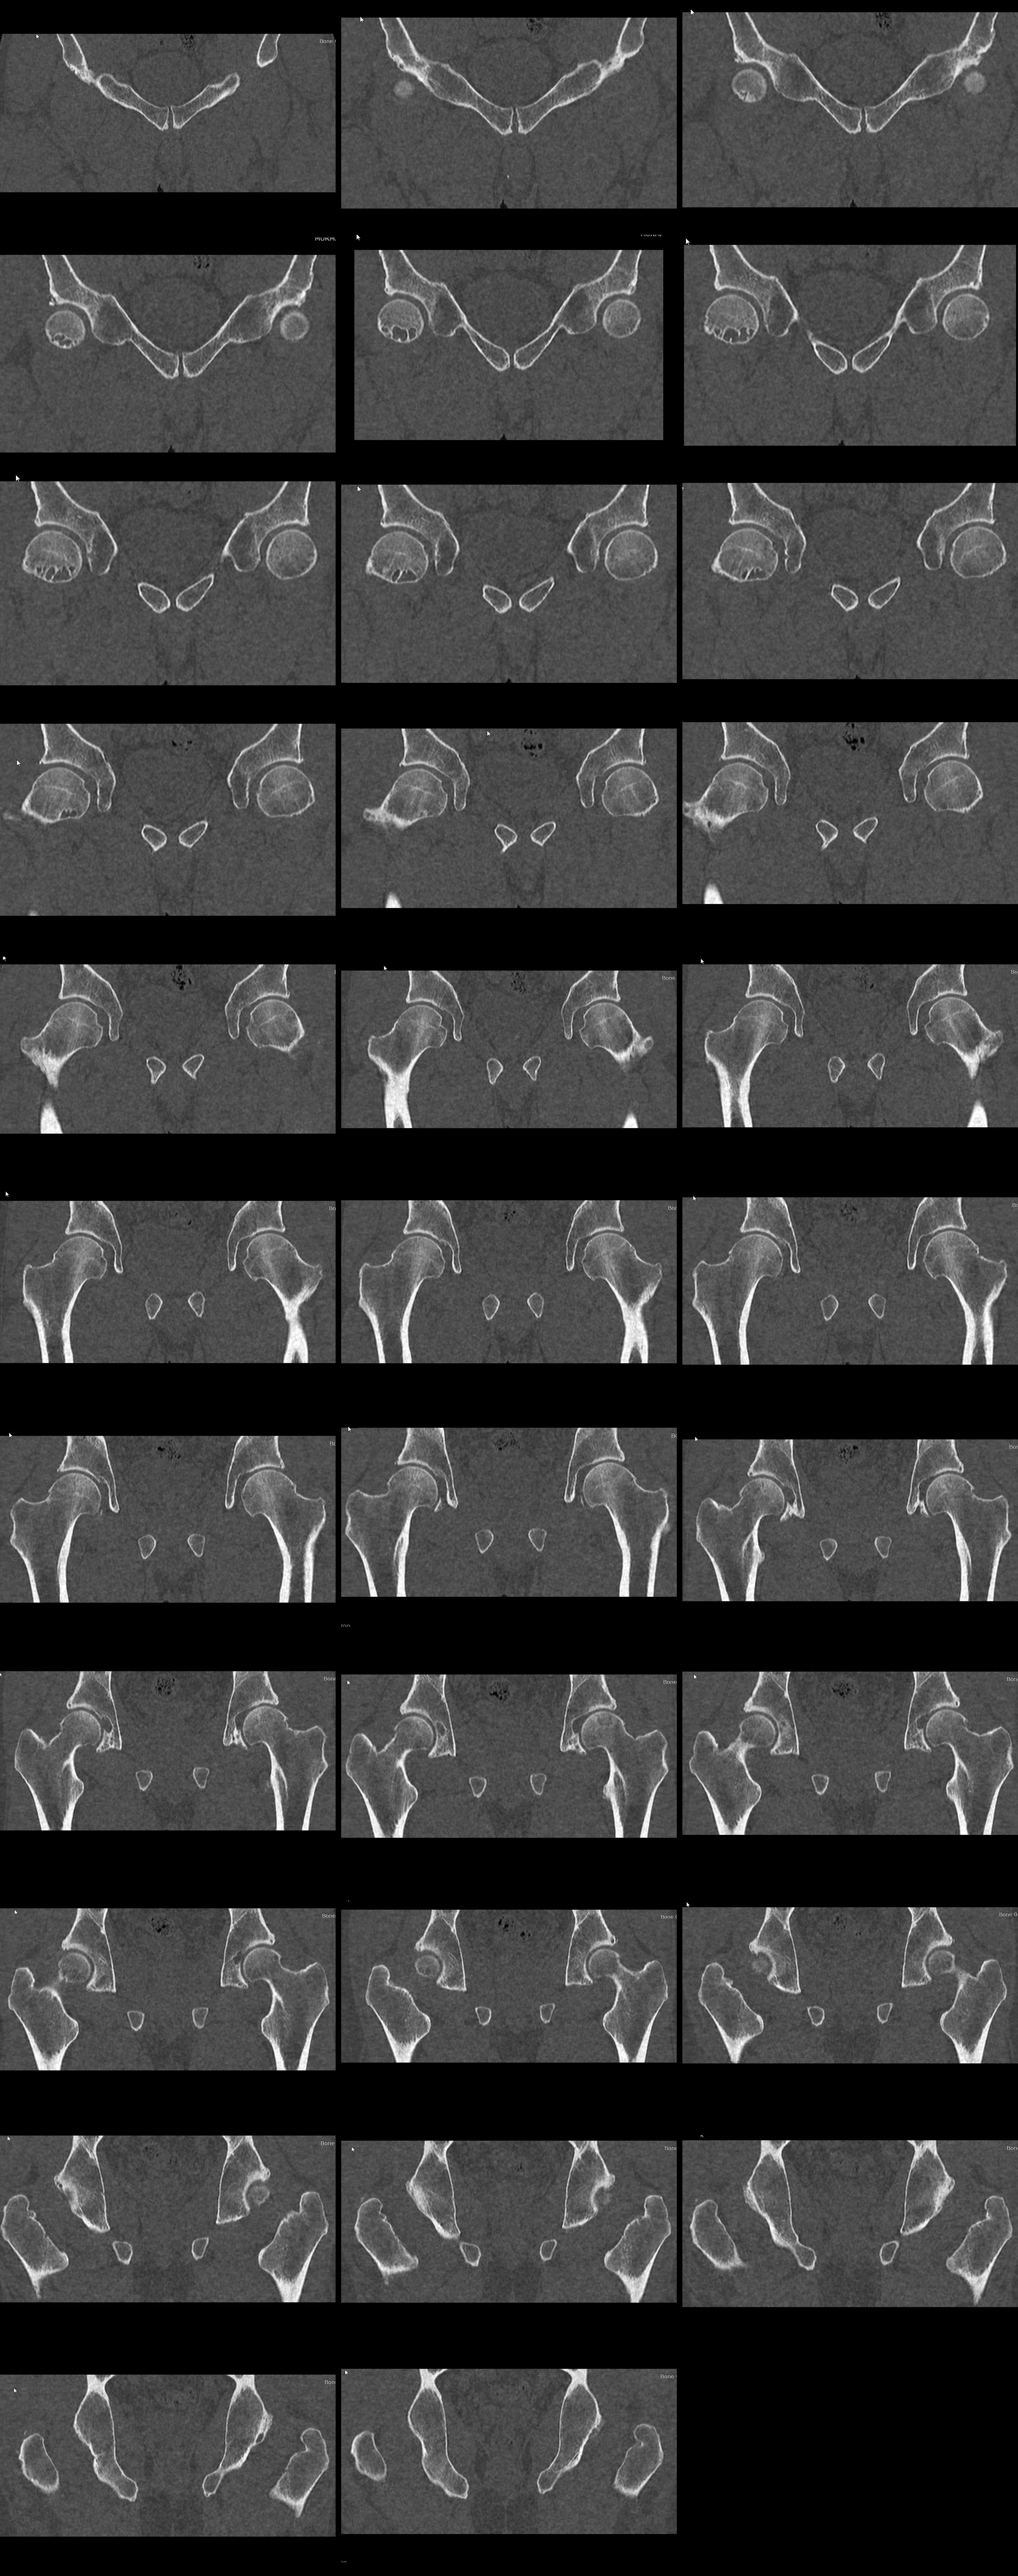

Для определения любой патологии необходимо начать с самых простых, и по необходимости надо добавить более сложные методы исследований. Как указали, что здесь не хватает обычной рентгенограммы тазобедренного сустава, где на обзорном снимке, кроме кисты, можно увидеть анатомические соотношения. Соотношения может указать на механизм образования, например Hip Impingment!

При impingment одной из причин образования кисты в головке является напряжение постоянной травмой, т.е соударения за счет выступающей анатомической части. На месте напряжения сперва накапливается жидкость и образуется стенка кисты. Через тонкие стенки кисты может пройзойти перелом!

Киста, образовавшаеся вследствие impingement, иногда имеет симметричность на вертлужной стороне, и поэтому потребуется не отрывки, а полное КТ исследование с включением поперечных, сагиттальных и коронарных срезов.

я почти уверен, что это FAI, локализация, анамнез и клиника не сильно типичные для AVN, тем более тайский бокс - там много ударов ногами в крайних положениях с большим усилием. Постоянные соударения и перегрузка как раз в этой зоне при высоких ударах - вот и кисты. Видел ранние импинджементы у тхэквондистов (там еще больше "работы ногами") в еще более молодом возрасте. Мне тоже показалось симметричная проблема в вертлужной впадине, пока может и не киста, но разрежение костной ткани уже есть.

Выкладываю доп.КТ и сегодня выполним рентгенографию.

Если я правильно понял, по КТ - признаки CAM-импиджмента. Но киста располагается по передне-нижней поверхности шейки и головки бедра. Может ли она являться результатом импиджмента?